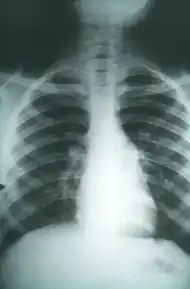

Chest X-rays rarely demonstrate nodules or cavities in the lungs, but these images commonly demonstrate lung opacification, pleural effusions, or enlargement of lymph nodes associated with the lungs.[1] Computed tomography scans of the chest are more sensitive than chest X-rays to detect these changes.[1]